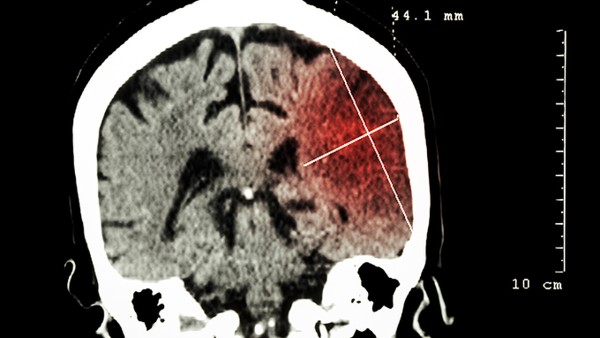

小脑是维持人体平衡的大脑组织,一旦发生梗塞,会严重影响患者的身体平衡。小脑梗塞归属于后循环缺血,绝大多数病人在发病前沒有明显的征兆,病程较急,但病症持续时间较短,非常容易反复发作,针对小脑梗塞出現的病症应严苛依据脑梗塞的医治方案积极主动医治。